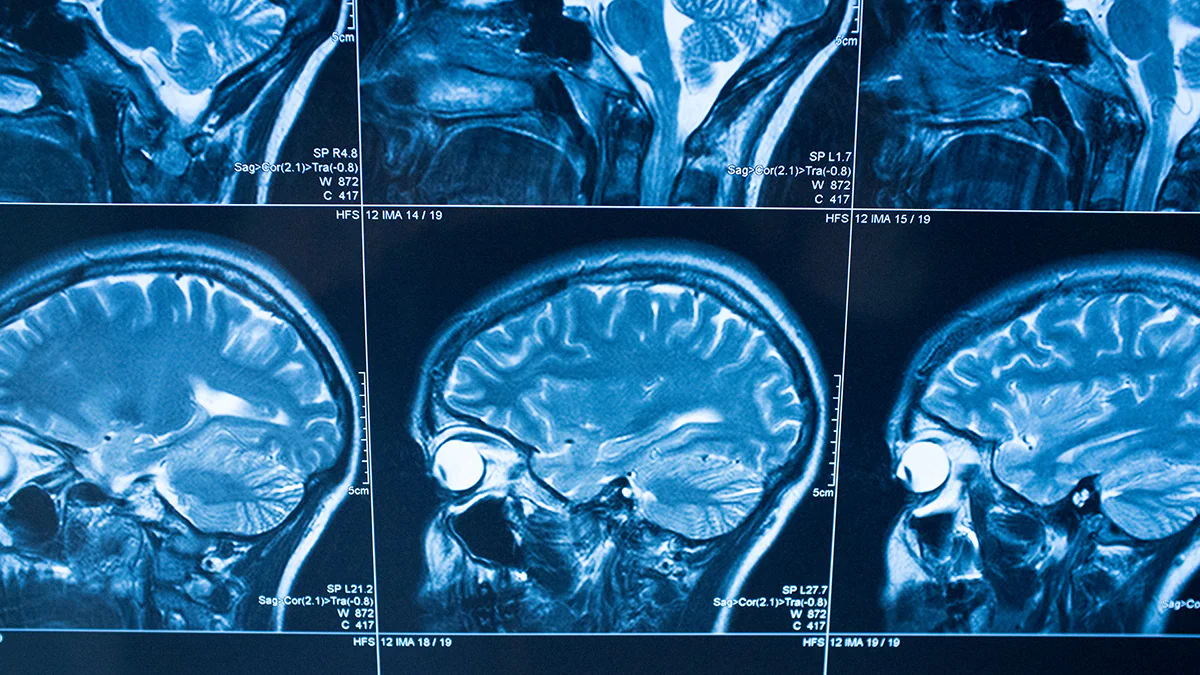

A stroke, sometimes called a brain attack, occurs when something blocks blood supply to part of the brain or when a blood vessel in the brain bursts.

In either case, parts of the brain become damaged or die. A stroke can cause lasting brain damage, long-term disability, or even death.

The brain controls our movements, stores our memories, and is the source of our thoughts, emotions, and language. The brain also controls many functions of the body, like breathing and digestion.

To work properly, your brain needs oxygen. Your arteries deliver oxygen-rich blood to all parts of your brain. If something happens to block the flow of blood, brain cells start to die within minutes, because they can't get oxygen. This causes a stroke.